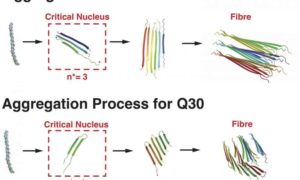

Come una proteina mutante può innescare malattie neurologiche

Gli scienziati della Rice University hanno scoperto nuovi dettagli su come una sequenza nucleotidica ripetuta nel gene che codifica per…

Svelati nuovi meccanismi molecolari nella malattia di Huntington

La malattia di Huntington è una malattia ereditaria neurodegenerativa attualmente incurabile. Gli scienziati di tutto il mondo sono alla ricerca…